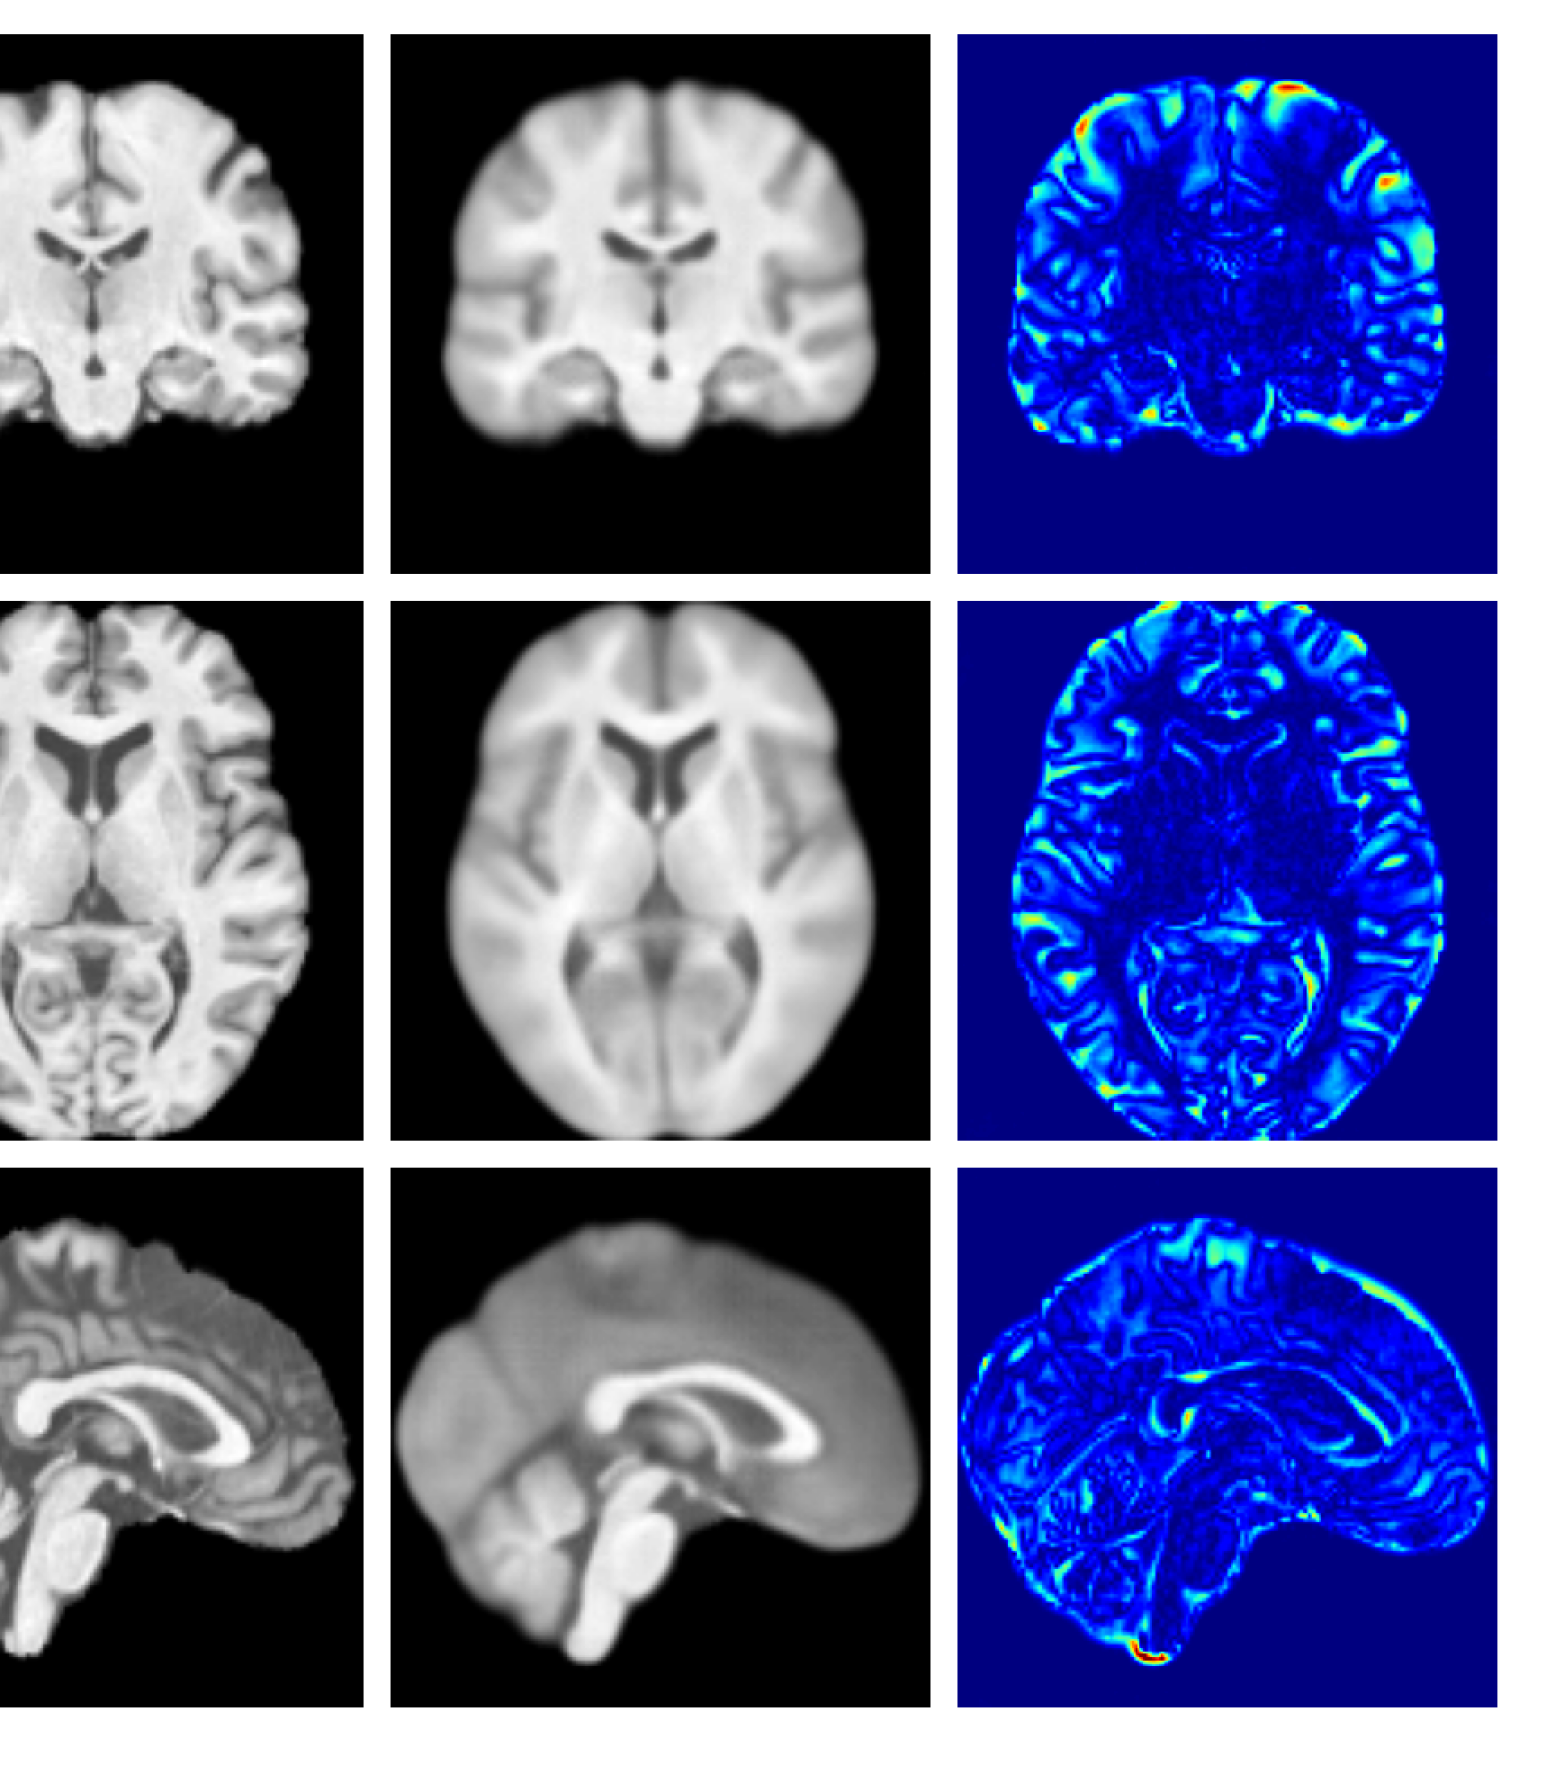

Figure 3: Example reconstructions and anomaly maps for a sample from the disease cohort of the UKBB dataset. Lesion and WMH are indicated in the original image by the red and yellow boxes respectively.

Figures 3 and 4, show example reconstructions and abnormality maps for a sample from the UKBB and UoTH datasets, respectively. Enlarged figures and additional example qualitative results for the ADNI dataset are available in the Supplementary. In Figure 3 we see that whilst all models are able to detect the lesion visible in the sagittal slice, the VAE, cVAE, LDM and LDM (TavgT_{avg}) produce very smooth outputs or lose defining characteristics and thus exhibit more false positives in healthy tissue. THOR and CADD provide the best results, with CADD better detecting white matter hypointensities (WMH). However, neither method fully inpaints all WMH, potentially due to presence of WMH in the healthy training set.

Figures 8 and 9 are enlarged versions of Figures 3 and 4 respectively, with the latter now including results from all compared methods. Figure 10 provides example reconstructions and anomaly maps for an AD subject from the ADNI disease cohort.

Refer to caption

Figure 8: Enlarged example reconstructions and anomaly maps for a sample from the disease cohort of the UKBB dataset. Lesion and WMH are indicated in the original image by the red and yellow boxes respectively.